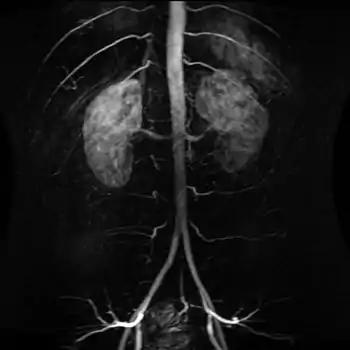

| The abdominal aorta and its branches. | |

آئورت یا بزرگسرخرگ[1] (به انگلیسی: aorta) سرخرگ اصلی خونرساننده به بدن است. از این شریان، شریانهای متعددی منشعب میشوند که خون را به سراسر بدن میرسانند. آئورت سه لایه داخلی، میانی و خارجی دارد که از کلاژن، الاستین و عضلات صاف ساخته شدهاند. آئورت شکمی (به انگلیسی: Abdominal aorta) بزرگترین قسمت از رگ آئورت و در ناحیهٔ شکمی بدن (از دهانهٔ دیافراگم تا کمر) (به انگلیسی: abdominal cavity) قرار دارد. به عنوان بخشی از آئورت، آئورت شکمی در اصل ادامهٔ بزرگسرخرگ پایینرو یا آئورت نزولی، (به انگلیسی: descending aorta) است که در ناحیهٔ قفسه سینه قرار دارد.